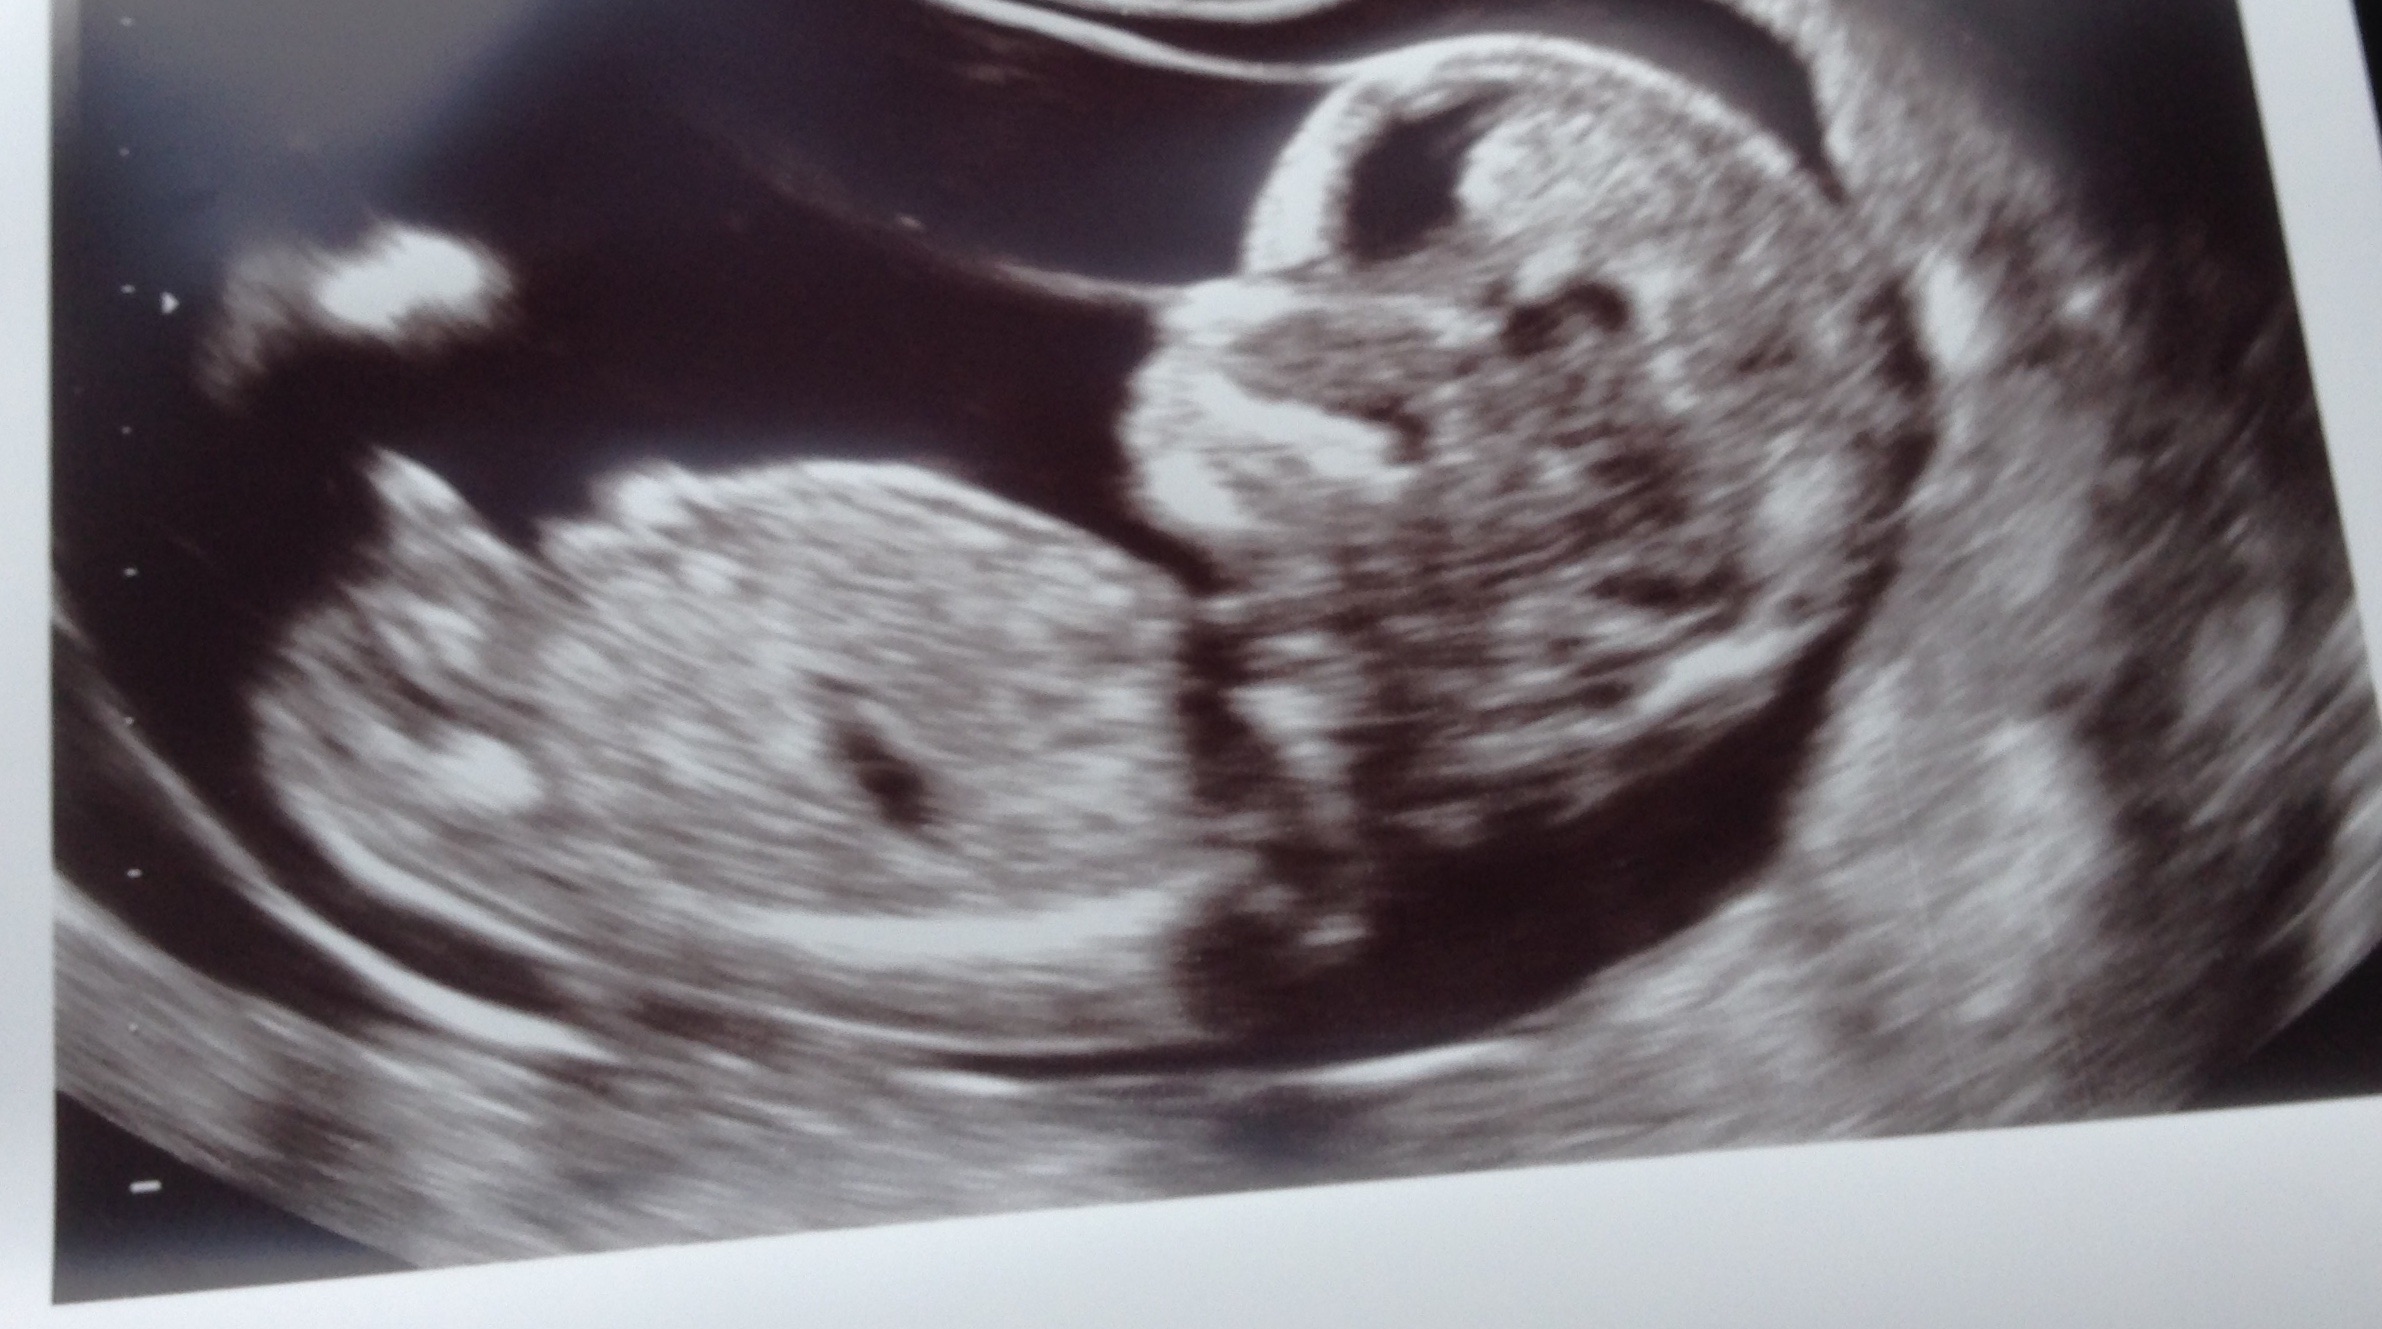

Please help me :) male or female? Attachment 24262Attachment 24263

That's a perfect boy nub! Congrats!

Thankyou all for your opinions!! We have our fingers crossed for boy :) we already have 2 beautiful healthy girls. I don't rember seeing these parts on our girls :) I can't wait to find out but need to wait another 8 weeks :(

Boy nub